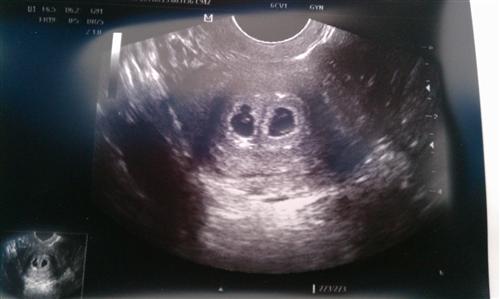

UPDATE: today is sonogram day!!!

And I am a nervous wreck!!!

Update: He saw 2 sacs, 2 fetal poles and 1 heartbeat, but he thinks the 2nd one should be there on Monday (was supposed to be Friday, but he called tonight to change it) so we have to go back then! DH and I both thought we saw the 2nd heartbeat, but what do we know? I cried all over Dr b then hugged and kissed him, lol!

Link to sono pic Image Attachment(s):